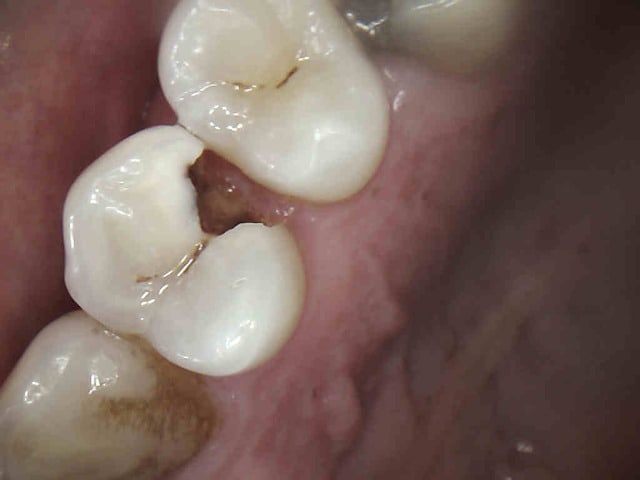

C'est un traitement conforme aux recommandations de la HAS. Celui ci n'est pas conforme : pourquoi ?

Et pourtant obturation à l'apex, thermo-compaction.

Il est au tarif secu ?? Sans digue .

Si on parle d'expertise medicale seule, il y a perte de chance par la non mise en place de la digue qui à elle seule entraine la responsabilité du praticien.

+ pas de reconstitution préendo.-)))